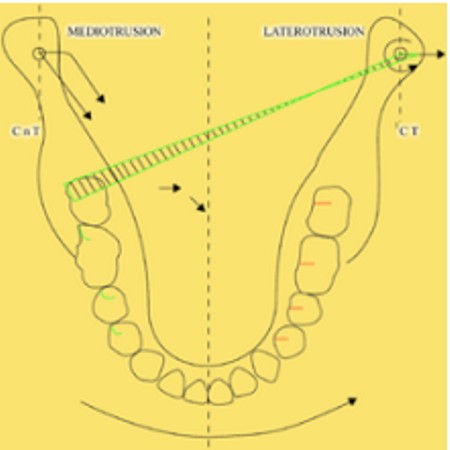

Primera Parte RESUMEN: La alta complejidad inherente a los procedimientos de Rehabilitación Oral, obligan al profesional que la ejerce a basarse en parámetros multidisciplinarios, a veces lo suficientemente intrincados que hacen imposible la práctica de la misma, sin la presencia en su mente de una clara concepción de la Oclusión. The extreme complexity of Oral Procedures, make it imperative for the working professional to rest on multidisciplinary parameters, sometimes so complex that make impossible its practice without the presence of a clear idea of Oclusion. DESARROLLO Suele ser sumamente árido el abordaje de un tema como Oclusión, desde la perspectiva de nuestro diario trabajo ,con todo el strees que este conlleva, con toda la lucha que significan citas, honorarios, diferentes personalidades de los pacientes, inquietudes de los mismos, etc. «LA MEJOR OCLUSIÓN ES LA QUE TIENE LA MEJOR DESOCLUSIÓN» Básicamente, podemos como desde hace ya muchos años se viene haciendo; clasificarlos en: A)Determinantes Posteriores (fijos) Más contemporáneamente, en: I-Mecanismos Primarios: A.T.M. GUIA ANTERIOR INCLINACIÓN DEL PLANO OCLUSAL CURVA SAGITAL DE SPEE FORMA DE LA ARCADA III-Mecanismos Elementales CRESTAS TRIANGULARES INTERNAS Analicemos cada uno de ellos: Es evidente, que la reproducción de las características de la A.T.M., en nuestro aliado fundamental, el Articulador; es imprescindible. Partiendo de la premisa de obtener una OCLUSIÓN MUTUAMENTE PROTEGIDA, para luego arribar al concepto de OCLUSIÓN MUTUAMENTE COMPARTIDA, concepto este que desarrollaremos durante el transcurso de las distintas entregas, analizaremos cada uno de los FACTORES DETERMINANTES DE LA OCLUSIÓN. El primero de ellos, por ser fijo e invariable, solo diremos que: son sus INCLINACIONES PLANARES, o sea : A-INCLINACIÓN DE LA TRAYECTORIA CONDILEA C-BENNET INMEDIATO articuladores totalmente ajustables) D-DISTANCIA INTERCONDILAR. En cuanto a la GUÍA ANTERIOR, mecanismo primario y por supuesto anterior, provee al cuerpo mandibular; del camino a recorrer durante las excursiones protrusivas y lateralidades, a través del vínculo entre las piezas dentarias anteriores, superiores e inferiores. En un corte sagital, podemos observar la relación entre estos donde vemos que se vinculan sin entrar en un contacto franco, sino más bien en una relación de vencindad muy intima a la que llamamos: PUNTO DE ACOPLAMIENTO. Otros factores fundamentales de la GUÍA ANTERIOR son : A-ALTURA FUNCIONAL B-PUNTO DE ACOPLAMIENTO En cuanto a los SURCOS, sabemos que durante una Transtrusión, las cúspides fundamentales generan surcos sobre las piezas que antagonizan. Dichos surcos proveen de una vía de escape a las cúspides antagonistas para evitar colisiones, con las indeseables fuerzas laterales cuya gravedad ya conocemos. MECANISMOS SECUNDARIOS La CURVA FRONTAL DE WILSON, se observa invertida a nivel de los caninos y de los primeros premolares. El PLANO OCLUSAL, en realidad no es ningún plano, sino la sumatoria de muchos MICROPLANOS, los cuales individualmente pueden constituir factores presentes en la OCLUSIÓN, pero auténticos problemas para la DISCLUSIÓN. La CURVA SAGITAL DE SPEE, denominada originariamente de BALKWIL-SPEE, fue concebida como una curva. El cuarto factor SECUNDARIO: el ANCHO DE LA ARCADA, es evidente que variando los ejes de rotación , alrededor de las diferentes distancias ;cambiará la dirección de los escapes (surcos), de los elementos que en el se muevan (cúspides). MECANISMOS ELEMENTALES Los CUATRO NIVELES DE OCLUSIÓN y las CRESTAS TRIANGULARES INTERNAS, constituyen de por si, la herramienta ejecutora de las funciones gnáticas. A- ELEVACIONES 1-Puntas Cuspídeas B-DEPRESIONES 1-Fosas SURCOS DE DESARROLLO De las CRESTAS TRIANGULARES INTERNAS, acentuamos su importancia en ellas dado que son las efectoras finales de la molienda, y su triangularidad debe tener su base partiendo del surco y su vértice terminando en la Punta Cuspídea, condición importante para evitar colisiones durante la transtrusión (movimiento de lateralidad ). EFECTOS DE LA VARIABILIDAD DE LOS FACTORES DETERMINANTES DE LA OCLUSÍON Cada uno de los determinantes influye aumentando o disminuyendo tanto la DESOCLUSIÓN como la ALTURA CUSPÍDEA INCLINACIÓN DE LA TRAYECTORIA SAGITAL INCLINACIÓN DEL PLANO OCLUSAL RADIO DE CURVATURA DE LA ÁNGULO DE LA TRAYECTORIA ALTURA DEL PUNTO DE LATERO SURTRUSIÓN / MOV. DE BENNET INMEDIATO CURVA FRONTAL DE WILSON SURCOS BIBLIOGRAFÍA Dibujos y esquemas tomados del libro: Oclusión Orgánica…un camino hacia la Rehabilitación Oral. 1)William Mc Horris,B.S.,D.D.S. Oclusión. Con especial énfasis sobre :El rol funcional y parafuncional de los dientes anteriores. 2)Von Spee , Craff(Anatomista alemán, describió la curva de compensación de la articulación de molares y premolares).CURVA DE SPEE 1.89 3)Stuart,D.»Some aspects of the inervation teeth.»Procedings of Royal Society of Medicine.20:1675,19274)Muhleman,H. y Savdir,S»Tooth movility-its causes and significance»Journal of Periodontology ,36:153,Marzo ,Abril,1965. 4)Muhleman,H. Y Savdir,S»Toothmovility its causes and significance» Journal of Periodontology,36:153,marzo,abril,1965. 5-Oclusión y Diagnóstico en Rehabilitación Oral. 6-Anatomia Odontológica. -A contribution to the study of the movementes of the mandible. 8-Celenza F.W, Nadeskin J.F.,Oclusión.Situación actual. 9-D´Amico 10-Dawson P.E. 11-Huffman -Regenos. 12-Hobo S.-Takayama H.A. 13-Lucia V.O 14-Mc Horris. 15-Mc Horris. 13-Posselt U. 16-Stuart C. 17-Vartan Veshnilian

Estos no son otra cosa que Arcos Góticos que adoptan distintas orientaciones según el lado hacia el cual se mueve la mandibula, y su angulación dependerá de la distancia a que se encuentren del eje vertical alrededor del cual roten.

Estos surcos reciben el nombre de :TRABAJO, NO TRABAJO y PROPULSIÓN ,según la acción ejercida por la cúspide.

Los surcos de Trabajo (ST)en rojo, No Trabajo (SNT) en verde, y Propulsión (SP) en azul, provéen de vías de escape a las cúspides durante la Transtrusión.